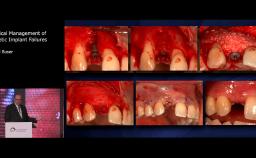

Extraction Site Bone Graft and Immediate Implant Placement in the Esthetic Zone

Zaid H Baqain

Patient expectations continue to increase, with the majority of patients expecting to have immediate replacement of missing teeth. This lecture provides a sound understanding of the key factors surrounding immediate implant placement. Advantages and disadvantages of this approach are discussed, using various cases to illustrate key points. Factors influencing esthetic outcome are discussed, with a good selection of evidence based information being presented.